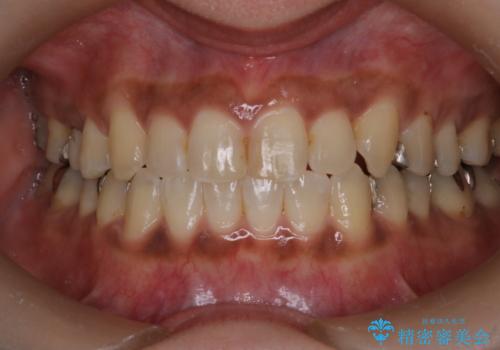

【インビザライン】前歯の凸凹をなおしたい

- 前歯の凸凹を主訴に来院されました。

インビザライン にて治療を行い、歯並びの改善を行うことができました。